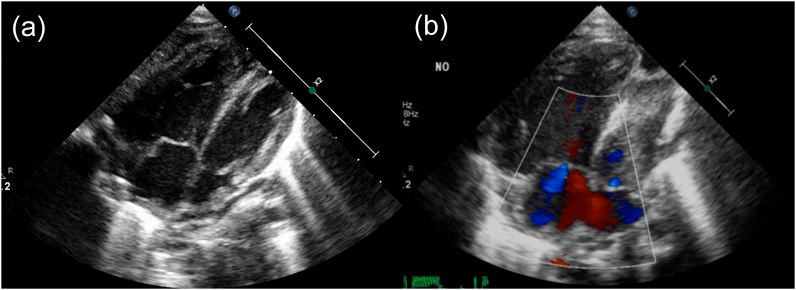

肥大型心筋症を合併した心房中隔欠損症に対して開窓付閉鎖術が奏功した1例Fenestrated Closure of an Atrial Septal Defect for Left Ventricular Diastolic Dysfunction in an Early Infant with Hypertrophic Cardiomyopathy